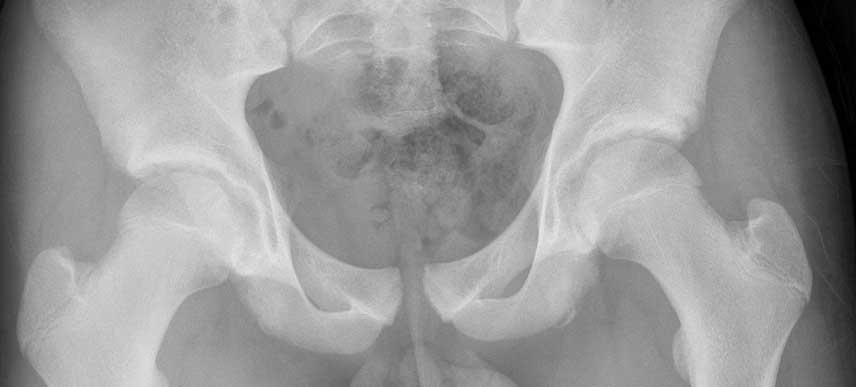

Symphysis-Pubis-Diastasis

Semasa hamil, ujian x-ray selalunya tidak dilakukan, jadi doktor anda boleh membuat ujian ultrasound dengan mengukur ruang antara tulang pelvis. Tetapi jika x-ray mungkin akan disyorkan untuk mendapat diagnosa yang tepat terutama sekiranya kesakitan anda adalah ketara. Jangan risau sinar x-ray tunggal tidak akan memberikan kesan sampingan terhadap bayi anda walau anda hamil.